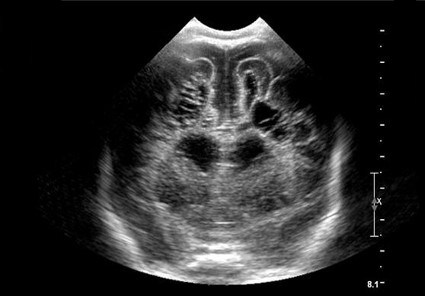

Neonatology Grade 4 PVL 1 Image